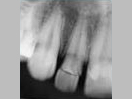

X-ray

Pre-Operation